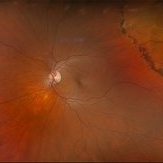

Optomap RGB of a 62-year-old man with a retinal detachment with a single break in the left eye. Patient has a previously treated HSRT in the left eye. Surgery was recommended. Patient is to continue follow up care post operatively.

Photographer: Kimberly Wakester, COA, OCT-C

Imaging device: Optos California

Condition/keywords: RD, retinal tear